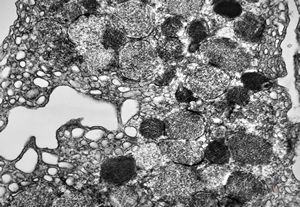

F, 46y. | verruca vulgaris … intranuclear virions

F, 46y. | verruca vulgaris … intranuclear virions

F, 46y. | verruca vulgaris … intranuclear virions